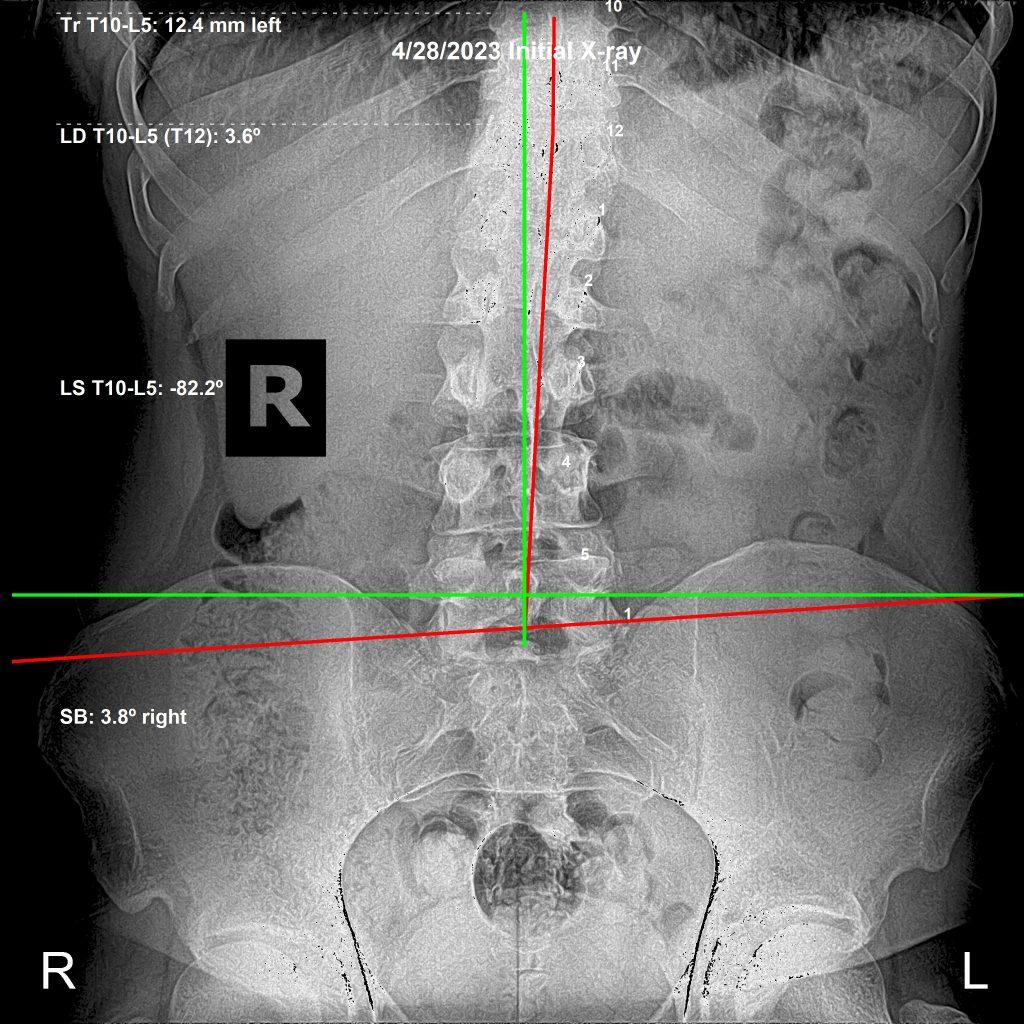

AP lumbar X-ray initial — Rochet Family Chiropractic

AP View — Initial

All of these new issues are related. We are kinetic chains — everything connected through motion. As his spine changed, specifically his pelvis, other areas appeared worse on film — even though functionally he was improving.